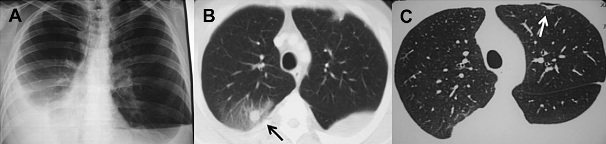

(圖:風濕性關節(jié)炎肺部影像學異常1例)

2、肺炎和肺纖維化:少數風濕性關節(jié)炎患者會出現發(fā)熱、咳嗽,病情進展時可出現進行性的呼吸困難,手指指端粗大,胸部X光片顯示:早期為肺門向雙側肺呈扇形網狀浸潤,后期為彌漫性、蜂窩狀陰影。肺纖維化男性較多見,多在風濕性關節(jié)炎發(fā)作后5~10年發(fā)病,也有先從肺部發(fā)病的。

3、肺風濕結節(jié):風濕性關節(jié)炎患者可在胸膜下,肺實質內多發(fā)性小結節(jié)陰影,也可單發(fā),前者可融合成塊狀,3~7毫米大小,后者為圓形,1~2厘米大小。肺中結節(jié)的出現、消失和空洞的愈合吸收與風濕性關節(jié)炎活動性和皮下結節(jié)的出現、消失基本同步。